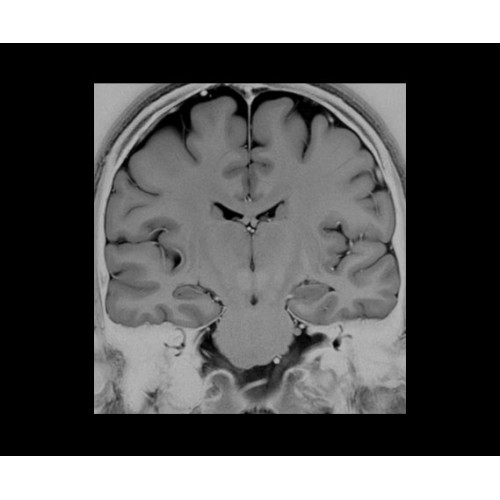

SIGNA PET/MR 3.0T — это гибридная система, в которой совмещаются две принципиально разные технологии — магнитно-резонансную томографию (МРТ) и позитронно-эмиссионную томографию (ПЭТ). Система отличающийся высокой чувствительностью и эффективностью и предназначена для диагностики в области онкологии, неврологии, кардио-васкулярных исследований, исследований воспалительных процессов.

Компания GE Healthcare представляет революционную, полностью интегрированную систему SIGNA PET/MR1, в которой сочетаются времяпролетная технология (TOF) и возможности напряженности магнитного поля 3.0 Тл. Мы поможем вам поднять исследования на более высокий уровень. SIGNA PET/MR позволяет достичь впечатляющей точности и скорости исследований, а благодаря новейшей технологии реконструкции Q.Clear2 качество изображений улучшается в два раза. Кроме того, в систему включен полный набор клинических приложений и гибких катушек для проведения любых видов исследования, открывая для вас возможности визуализации, о которых вы даже не догадывались.

Система SIGNA PET/MR предлагает впечатляющие клинические возможности и открывает доступ к наиболее полным пакетам программных приложений.